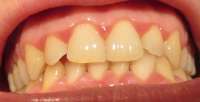

>>511739 (OP)

Мои зубки. Запломбировал все дырки коих было много, но внешний вид всё равно оставлял желать лучшего, на последнем приёме у стоматолога спросил насчет отбеливания зубов, какие есть варианты и т.д. она мне ответила, что у меня и так фиговая эмаль и мне нельзя делать отбеливание, дальнейшие расспросы особых результатов не дали. Собственно вопрос - и вправду нет адекватного способа отбелить зубы без вреда для самих зубов? Не очень то хочется бегать желторотиком всю жизнь. И какие еще могут быть способы привести зубы в более привлекательный вид?

>>513114

На чистке зубов был? Что то у тебя между зубов какие то отложения. Или это еда?